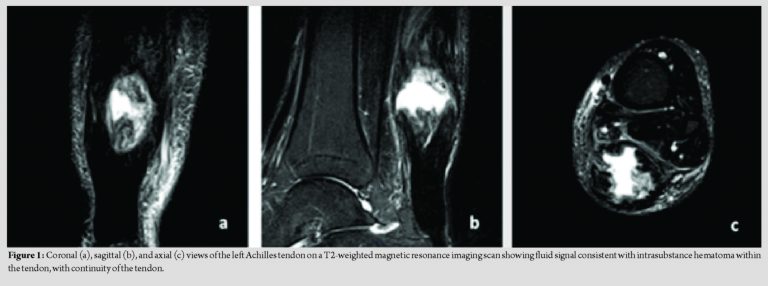

Urgent magnetic resonance imaging (MRI) was arranged due to the lack of a definitive diagnosis and to exclude infective or neoplastic causes of the swelling. The MRI scan showed a large fluid collection/hematoma intrasubstance in the Achilles tendon, located approximately 6 cm proximal from its insertion at the calcaneus, (Fig. 1). The unusual appearance of the scan prompted discussion of the case at a multidisciplinary team (MDT) meeting to guide the choice of treatment. The MDT suggested an organized hematoma or scar tissue as the most likely diagnosis; however, infection still had to be definitively excluded. The recommendation was to proceed with surgical exploration of the swelling with the aim of obtaining tissue samples for definitive diagnosis. Treatment options were discussed with the patient, including conservative treatment through to surgical intervention including synthetic options for tendon reconstruction. Following this, the decision was made to proceed with surgical arthroscopic debridement of the tendon. Needle aspiration of the swelling was performed and did not reveal a fresh hematoma. Two portals, one proximal and one distal to the swelling, were created in the left Achilles tendon. Decompression of the swelling was achieved using an arthroscopic technique. Tissue biopsies were taken for histology and microbiology. A gel-like material with scar tissue and abnormal tissue architecture was seen in this affected area of the tendon. Normal tendon tissue was visualized adjacent to the abnormal area. The histology report confirmed the specimen corresponded to tendon scar tissue with mild degenerate changes; fibro-fatty tissue was seen macroscopically. On microscopic examination, small fragments of connective tissue with mild degenerate myxoid change but no significant inflammation were noted. Postoperatively, the patient was discharged home on the same day and was advised to mobilize touch weight-bearing with crutches for 2 weeks. No external immobilization was required. Post-operative MRI views are shown in Fig. 2 with the intrasubstance hematoma now removed. At the 2-week follow-up, he was pleased with the progress, the wound was healing well and sutures were removed. Physiotherapy was started at this stage without loading exercises. At 7 weeks postoperatively, the patient was doing well with no pain, was talking no analgesia and the swelling was significantly reduced compared to preoperatively levels. He was pleased with the results of the surgery and was discharged from surgery and physiotherapy.